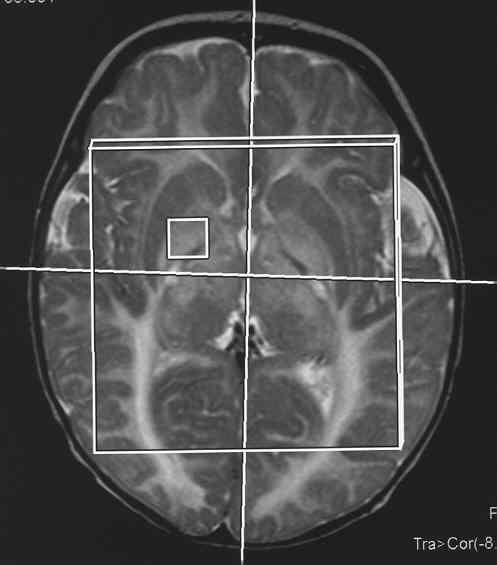

Abnormal MR spectroscopy (e.g. NAA, lactate)?